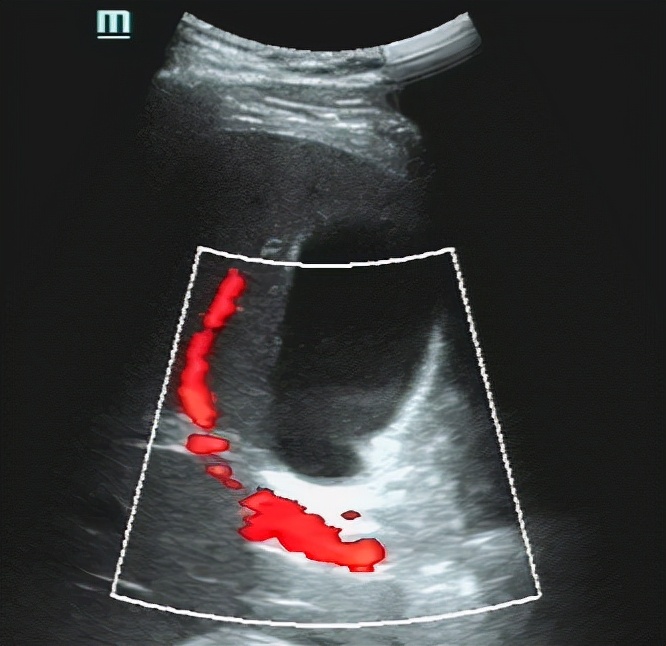

突然,在一个犄角旮旯发现个不明强回声。仿佛看到了黑暗中的黎明。。。

终于滚出来了